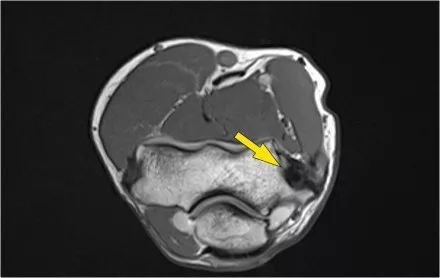

在下图可以看到,在左上方T1W图像中,伸肌中存在高信号脂肪,肌肉体积减少,这表明脂肪萎缩。右上方的轴向图像显示了旋后肌中更近端的质量。

矢状图像证实这是脂肪瘤。因此萎缩是骨间后神经受压的结果,骨间后神经是桡神经的一个分支。